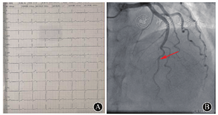

出院后,患者院外规范冠心病二级预防治疗,病情稳定,日常活动无胸痛发作。患者遵医嘱3个月后返院复查心电图提示前壁导联R波递增不良(图2A),超声心动图见左心室前壁室壁运动恢复正常,再次复查超敏肌钙蛋白Ⅰ结果阴性。冠状动脉造影提示前降支中远段狭窄病变明显改善(图2B)。

A:复查心电图提示ST段回落至基线,T波直立;B:复查造影提示前降支狭窄明显改善